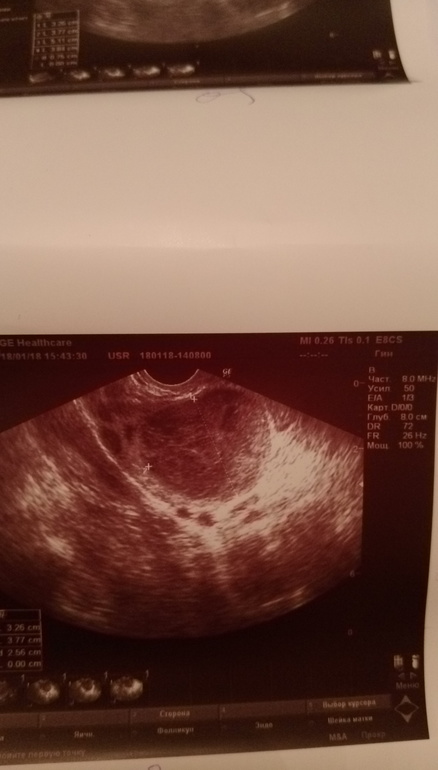

Дорогие девочки, сегодня 18 дц пошла я посмотреть была ли О. Хотя я ее на 14 дц поймала тестами, но так сказать подтвердить. А все так хорошо начиналось... Блин... сделала узи сегодня 2 раза, т.к. первое меня не устроило)))) мало что было понятно. Так вот что имеем... Киста жт (откуда взялась), на одном узи 22 мм на другом 30 с чем-то. Жидкость на одном есть, на другом нет((( Эндик на одном 12 мм, на другом 10 . Что вообще происходит кому верить? Возможна ли Б при таком узи, было активное планирование. И кто вообще с этим сталкивался. Я в шоке. Помогите советом. Фото узи под кат

Это второе узи! С первого фотки не брала))) они за отдельную плату!